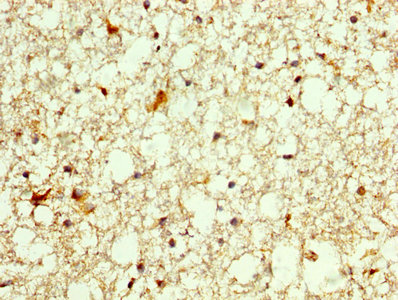

IHC image of CSB-PA017299LA01HU diluted at 1:250 and staining in paraffin-embedded human brain tissue performed on a Leica BondTM system. After dewaxing and hydration, antigen retrieval was mediated by high pressure in a citrate buffer (pH 6.0). Section was blocked with 10% normal goat serum 30min at RT. Then primary antibody (1% BSA) was incubated at 4°C overnight. The primary is detected by a biotinylated secondary antibody and visualized using an HRP conjugated SP system.